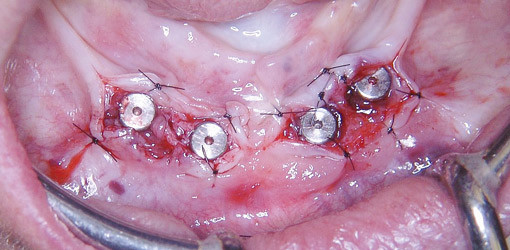

Eine 72-jährige Patientin mit unauffälliger Anamnese und sehr gutem Allgemeinzustand wurde 2006 alio loco mit vier interforaminalen Implantaten (3i Standardimplantate mit External Hex) versorgt. Nach einer komplikationslosen Osseointegrationsphase von vier Monaten sollte die Freilegung der Implantate erfolgen und die Patientin wurde von mir weiterbehandelt. Das intraorale klinische Bild zeigte eine deutliche Alveolarfortsatzatrophie mit Anhebung des Mundbodens über das Kammniveau und eine ungünstige Schleimhautsituation. Durch die relativ dünne Gingivaschicht waren die Implantate zu erahnen. Abbildung 1a zeigt die Situation unmittelbar vor der Implantatfreilegung.

Abb.1 a: Situation vor Implantatfreilegung. Massive Alveolarfortsatzatrophie mit Anhebung des Mundbodens und Verschiebung der Weichgewebsgrenzen. b: Zustand nach Laserkonditionierung des Weichgewebes. Durch die koagulierende Wirkung ist das OP-Gebiet übersichtlich. Implantate wurden zuvor freigelegt nach Spaltlappenpräparation und Fixierung der Attached Gingiva durch labiale und linguale Einzelknopfnähte. Mittels eines Diodenlasers (Fa. Oralia) wurde das Weichgewebe konditioniert und modelliert. Gleichzeitig erfolgte eine Koagulation des submukösen Gewebes. c: Zustand kurz vor Abformung mit individuellem Löffel. Nahtentfernung erfolgte eine Woche postoperativ. d: Abformpfosten in situ. e: Ein individuell gefräster Goldsteg wurde fixiert mit einem Drehmoment von 32 Ncm. f: Inkorporierte Stegprotese.

Bei der Schnittführung mit dem Skalpell ist genau zu beachten, wo sich befestigte Gingiva befindet. Ziel sollte es sein, das vorhandene „brauchbare“ Gewebe in gleichem Maße um die Implantate nach lingual bzw. labial zu bewegen. In diesem Fall war nach labial etwas mehr befestigte Gingiva vorzufinden und nach lingual durch den hohen Mundboden etwas weniger. Aus diesem Grund erfolgte die krestale Inzision etwas mehr nach labial, damit das Gewebe später nach lingual verlagert werden konnte. Wichtig ist es, eine Gingivabrücke zwischen den mittleren Implantaten bestehen zu lassen, damit eine spätere Verschiebung der mobilisierten Lappenanteile vermieden wird. Nach Infiltrationsanästhesie (UDS forte, Fa. Novartis) erfolgte eine Spaltlappenpräparation mit Verlagerung der Lappenanteile wie oben beschrieben nach lingual bzw. labial mit Nahtfixierung (Supramid 5/0, Fa. Stoma). Der Anteil zwischen den mobilisierten Lappen heilt per secundam. Abbildung 1b zeigt die fixierten Lappenanteile und die Verschlussschrauben der vier Implantate.